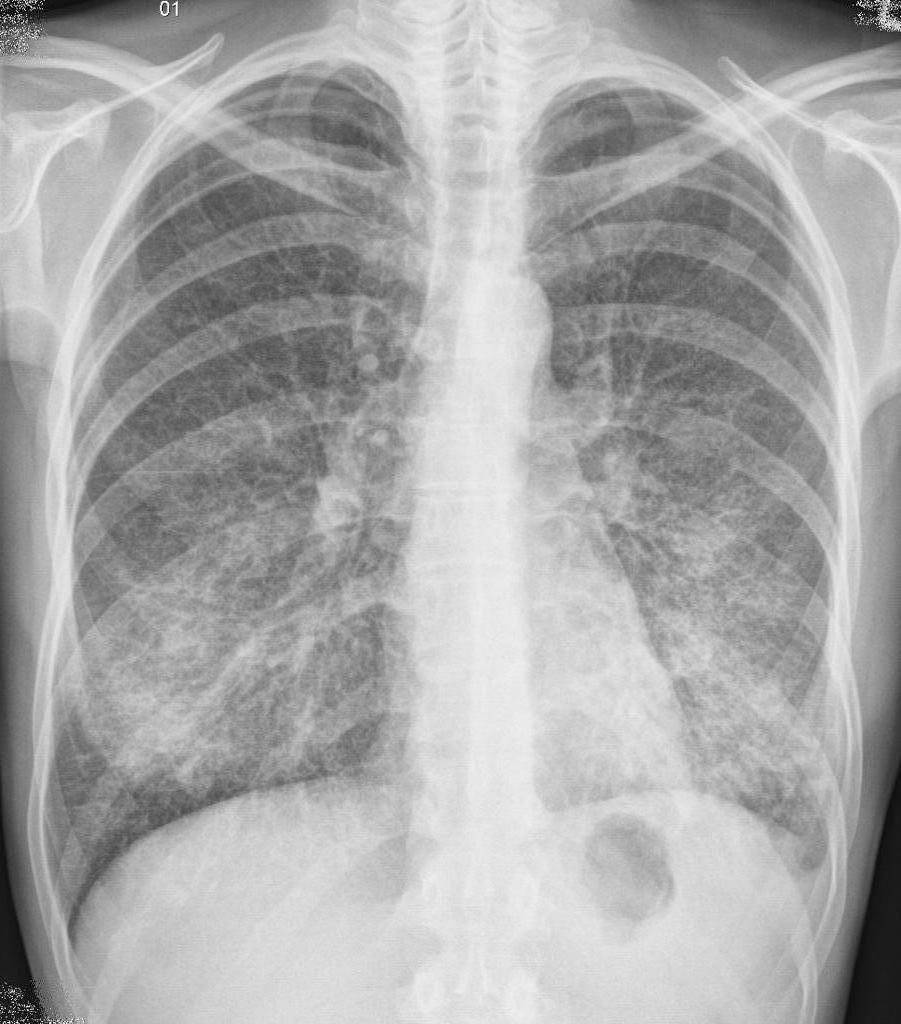

Habituellement, la maladie débute de manière aiguë, une toux apparaît avec des expectorations mucopuruleuses. Au cours de l'examen, on note un raccourcissement du son de percussion, un affaiblissement de la respiration bronchique, des râles humides à petits bulles, des crépitations. Dans les tests sanguins, on observe une leucocytose. Les rayons X montrent des zones d'infiltration.

- Roentgenography.

- deux ou plusieurs lobes sont affectés sur une radiographie;

- Degré sévère. Le patient présente des symptômes d'intoxication: la température corporelle est supérieure à 38 degrés. Une insuffisance respiratoire est observée, l'hémodynamique est perturbée. Avec des complications, un choc septique peut être diagnostiqué. Dans KLA, la leucopénie ou la leucocytose. L'infiltration est bilatérale, avec une augmentation rapide dans la zone touchée.